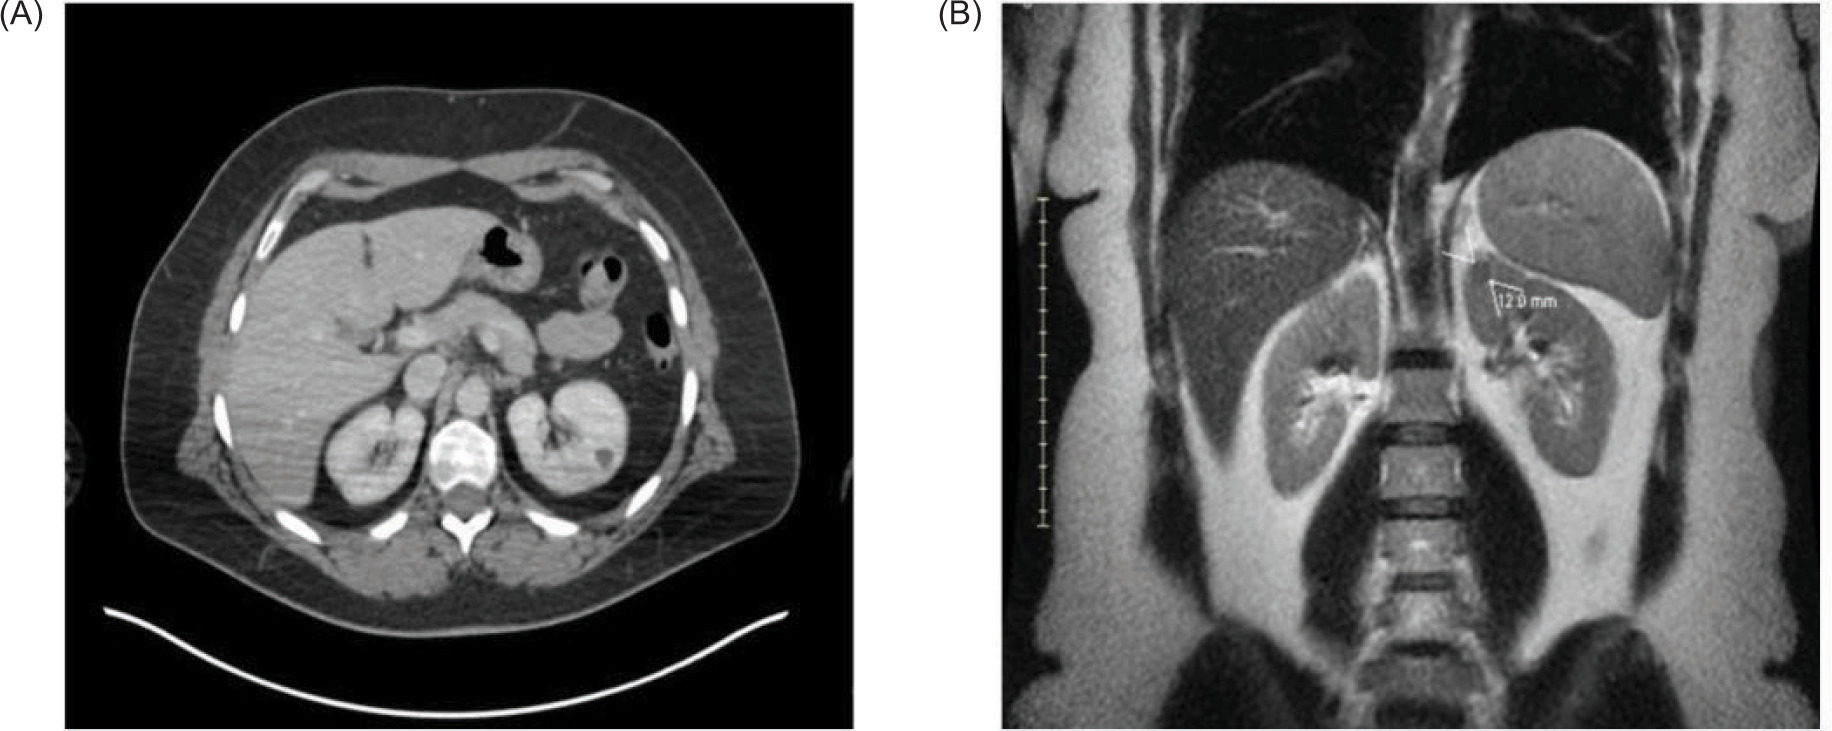

Figure 2: This is a histopathological image of the metastatic melanoma showing pigmented, atypical cells with abundant melanin (in dark circles). The tumor cells appear brown to black against the background of eosinophilic (pink-purple) H and E stain.